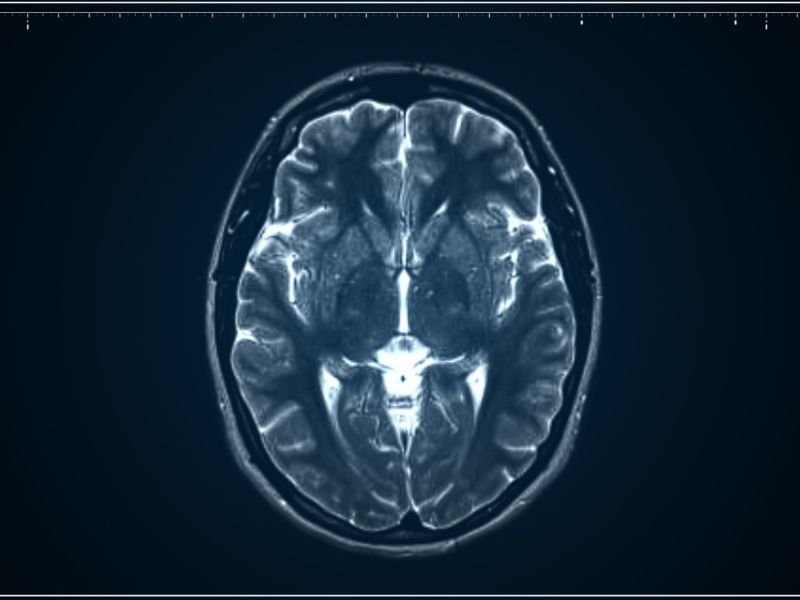

Infiltração para Dor de Cabeça em Criciúma A dor de cabeça é uma condição comum que pode afetar significativamente a qualidade de vida de uma pessoa. Em Criciúma, muitos pacientes buscam soluções para aliviar esse